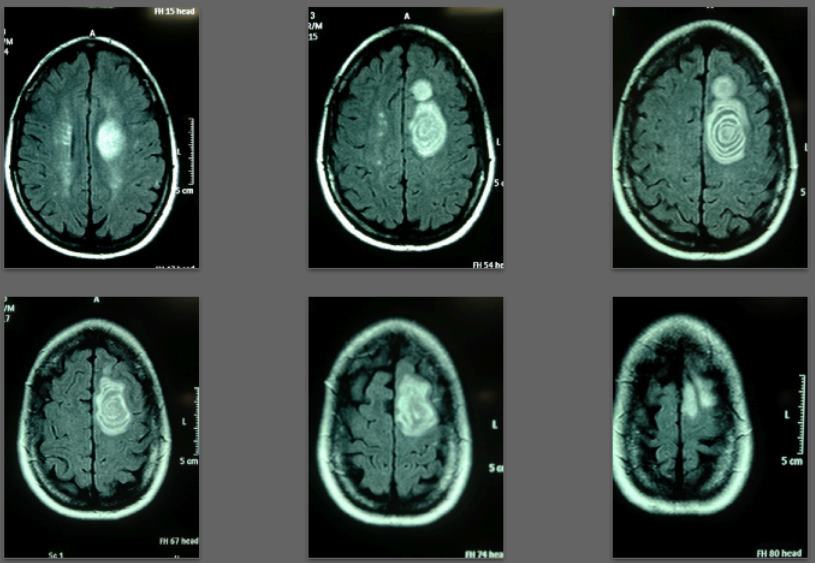

Before/after MRI images for one of 1,000+ patients of Dr. Coimbra

2008 Convulsive seizures Diagnosis: Balo’s concentric hemiparesis

Starting daily dose 25,000 IU; increased in stages to 80,000 IU on October 28, 2010. Asymptomatic since 2010.

2013 MRI